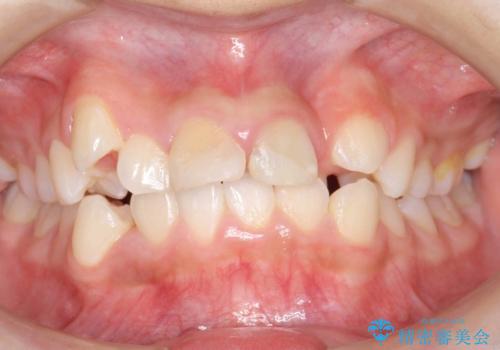

受け口 絶対に顎の手術はしたくない

- 受け口を主訴に来院。

下あごが大きく、顎の手術を含めた矯正をおすすめしましたが、手術は怖いので絶対にしたくないとのことでした。

歯並びのみを治す矯正は難しく、長期にわたる治療になるとご説明しました。

かみしめもあり、骨も固く、歯根も長いためなかなか歯が動かず、患者様も治療する側も忍耐を要する長期戦となりました。